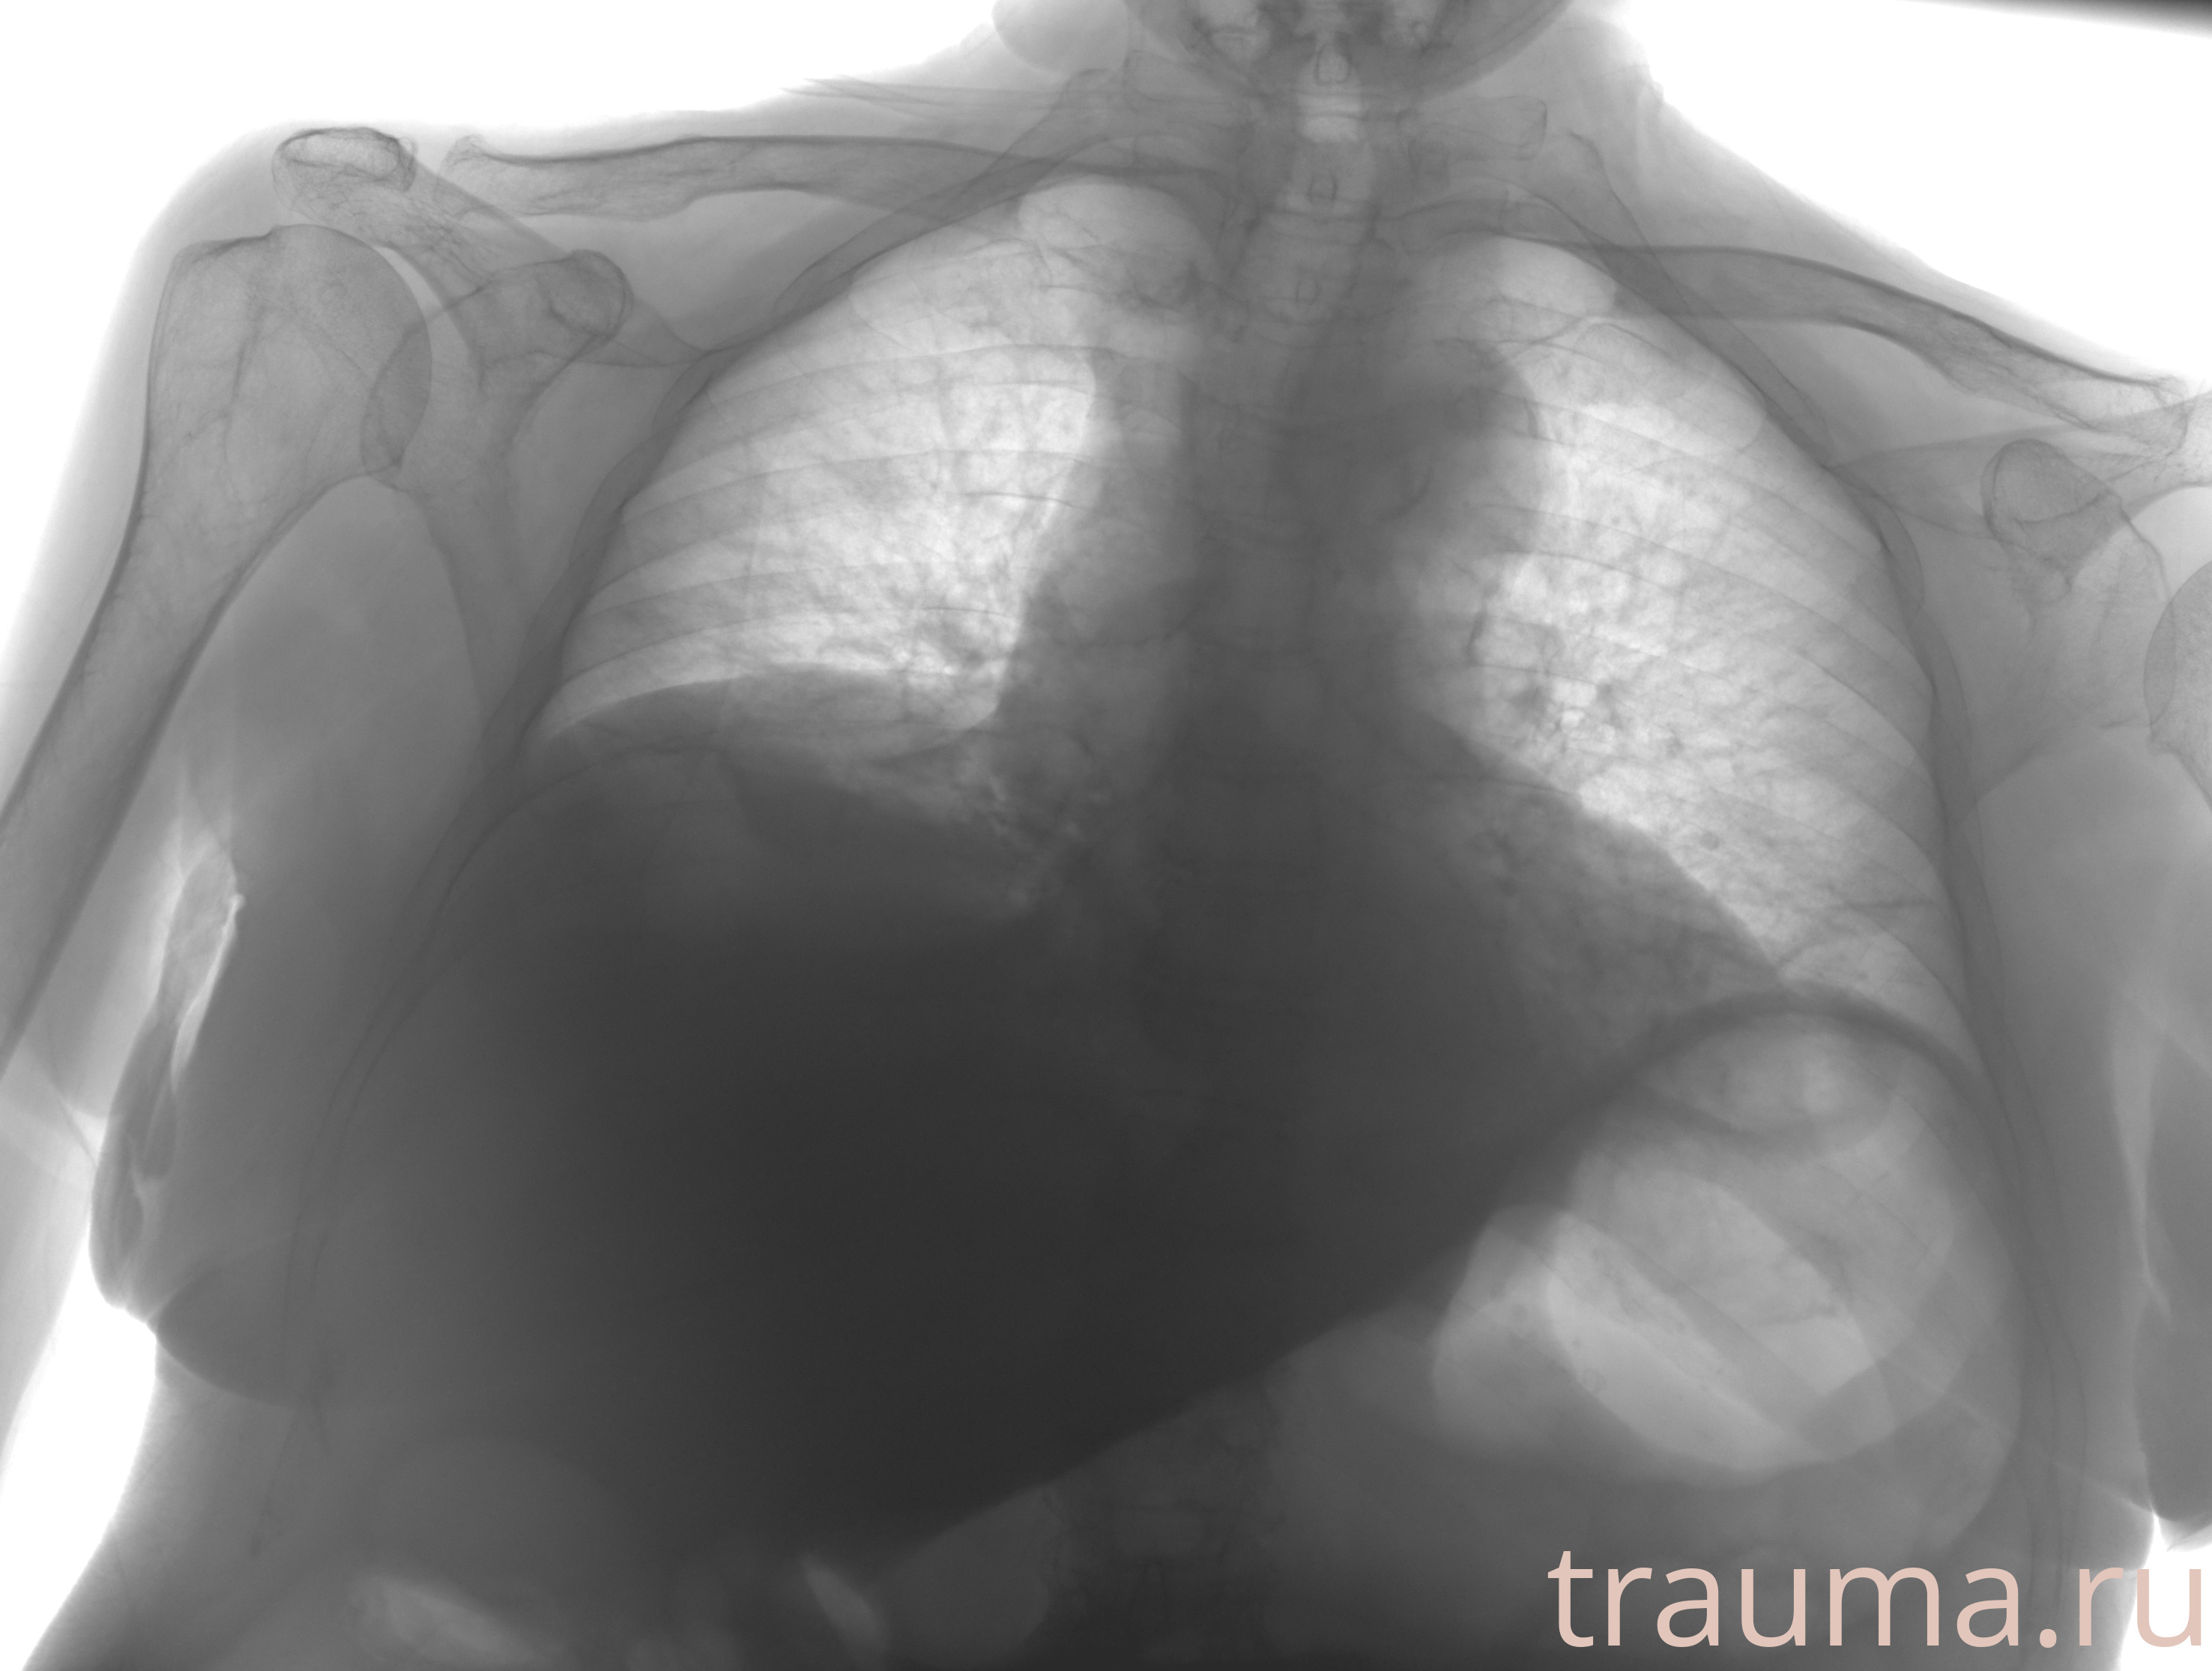

Рентген на дому: по вашему адресу приезжает врач-рентгенолог, травматолог-ортопед с мобильным рентгеновским аппаратом, проводит диагностику травмы или заболевания, делает необходимые рентгенограммы, дает рекомендации по дальнейшему лечению. Получить качественные снимки в домашних условиях возможно благодаря уникальной методике, разработанной МосРентген Центром для института  Склифосовского